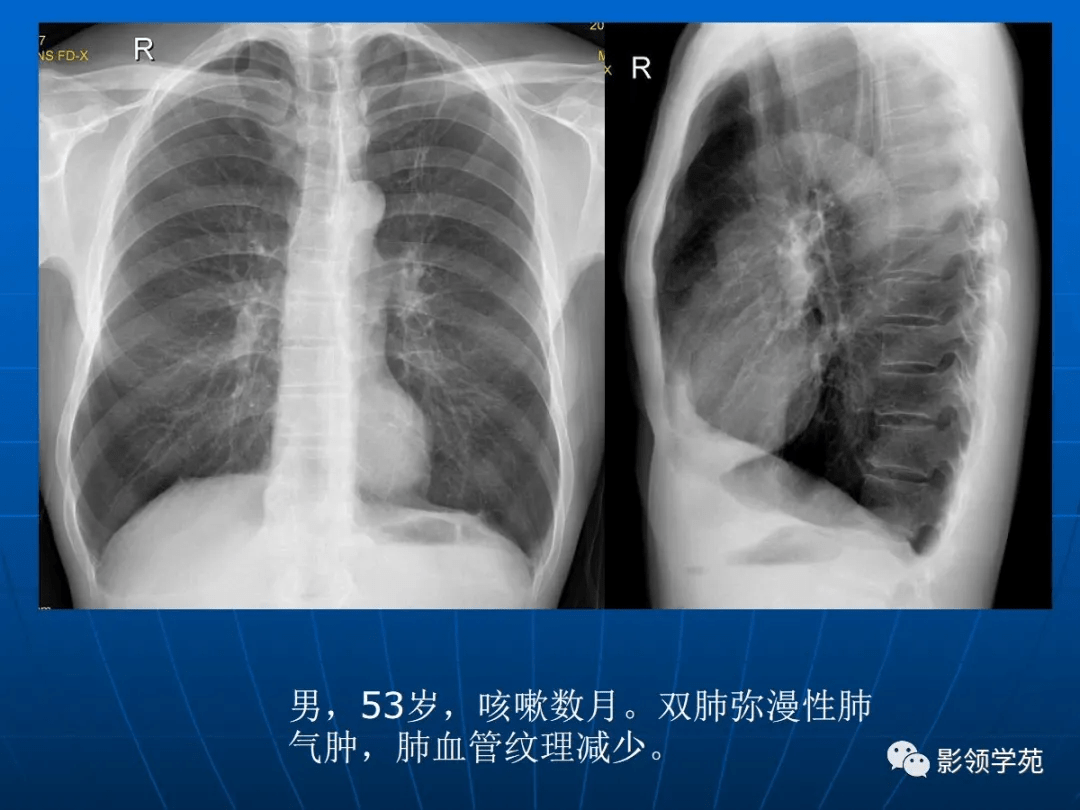

肺气肿的影像诊断